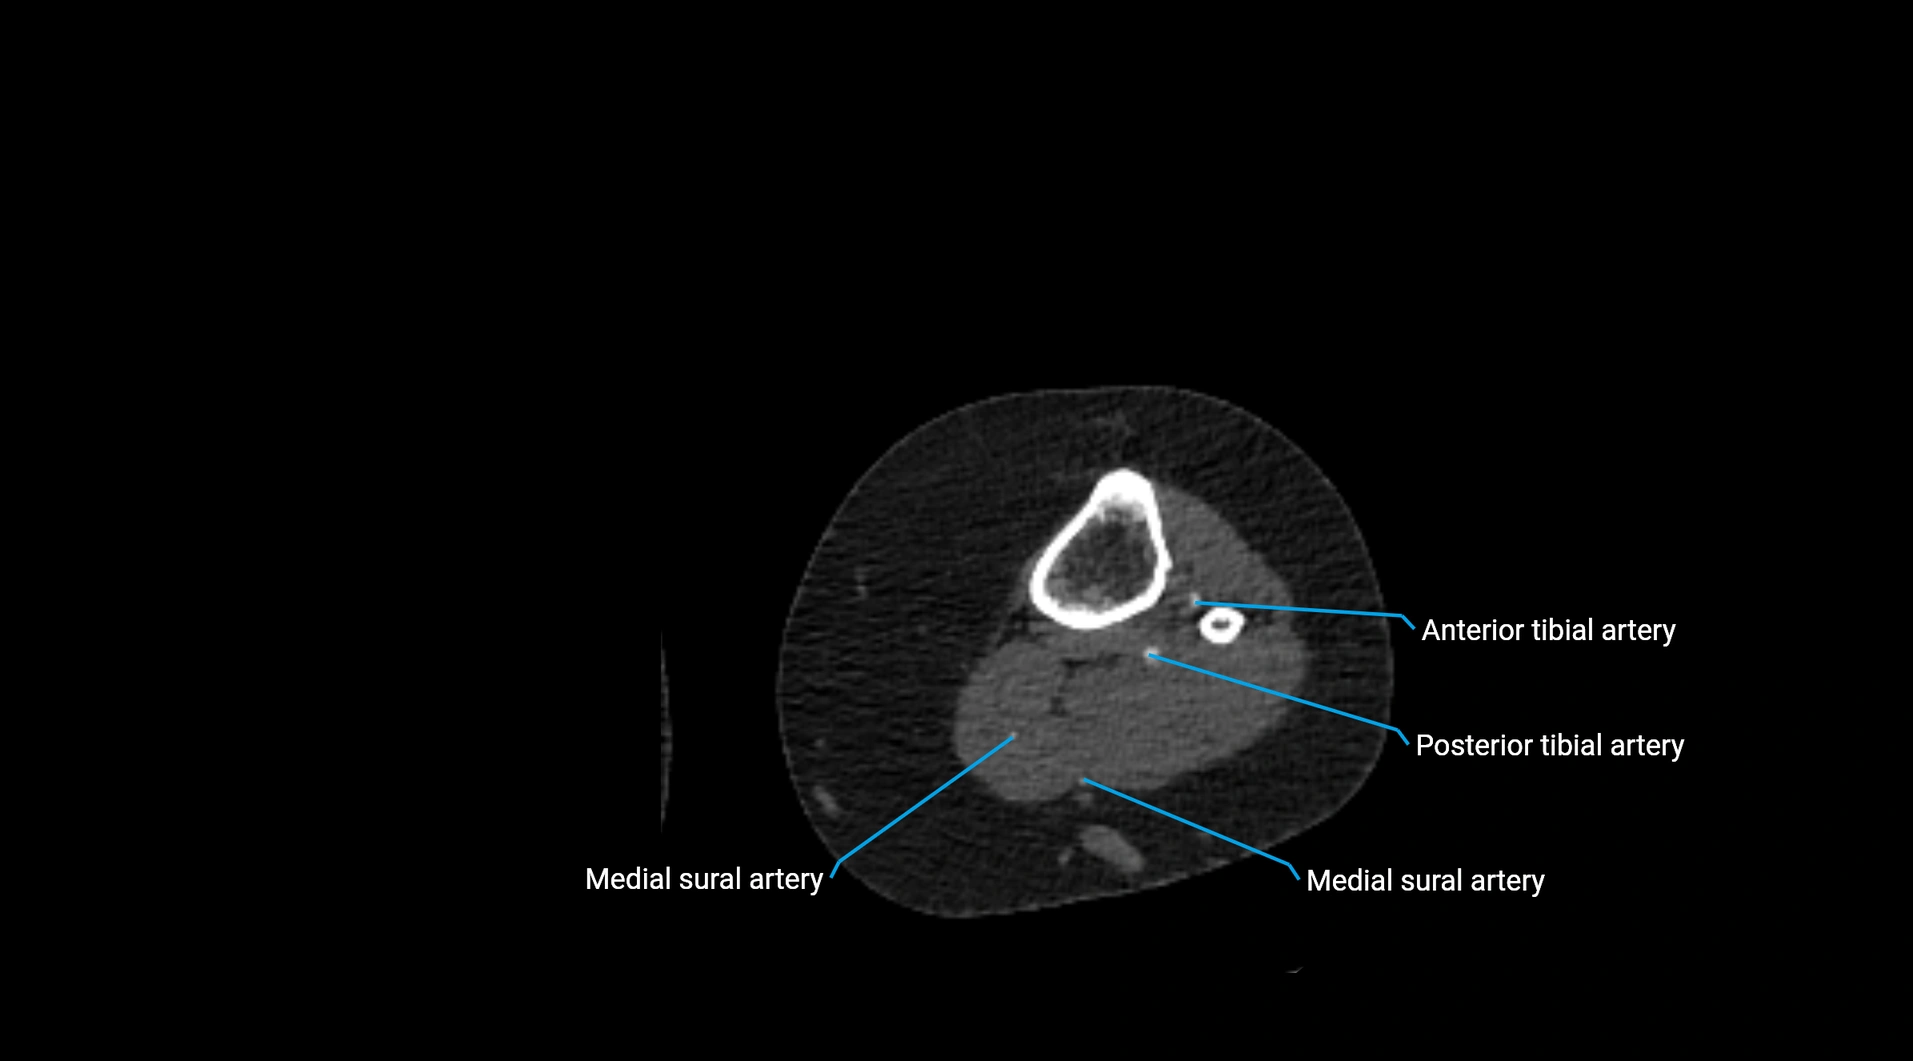

CT images

image